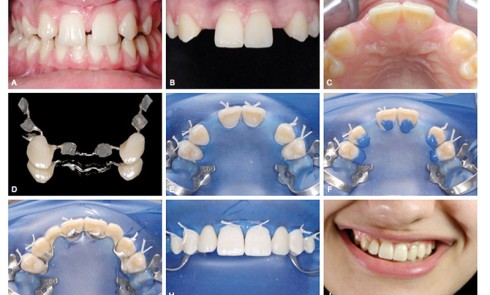

Article réservé à nos abonnés Temporisation des projets implantaires ou prothétiques : la solution T.O.B.B.I.

Comme nous venons de le lire dans ce numéro (Agénésies des incisives latérales : revoyons nos pratiques), nous sommes confrontés à...

Le cas présenté ici a été traité en orthodontie linguale. Il montre la nécessité d’interventions pluridisciplinaires préméditées afin d’obtenir un...